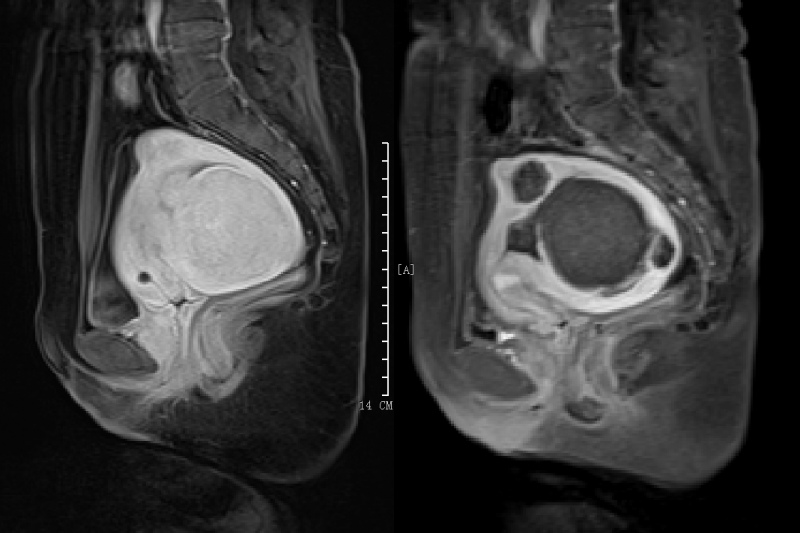

近日,陈女士经常觉得头晕疲劳、四肢乏力,便到惠州市第三人民医院就诊。经前核磁共振提示为多发性子宫肌瘤,最大位于后壁肌壁间,大小为74mm×63mm×69mm,粘膜下见一“0型”肌瘤,直径约2cm,前壁见数个小肌瘤,最大直径约3cm,且检查发现血红蛋白含量82g/L,为中度贫血。

术前MRI提示多发子宫肌瘤

术后MRI对比图